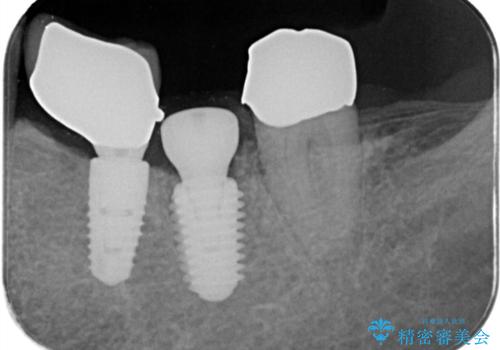

- 「歯を咬むと痛い」を主訴に来院された患者様です。 CTを撮ると歯根が縦に真っ二つに割れている状態で、歯周ポケットも10㎜を超える状態でした。

歯の保存は困難と診断しインプラントで治療を行いました。1Dayインプラントの適応だったので、抜歯した当日にインプラントを埋入しました。

1Dayインプラントは低侵襲なので痛みもほとんどありません。従来のインプラント治療だと1年弱かかるのが、3ヵ月で治療を終える事が出来ました。